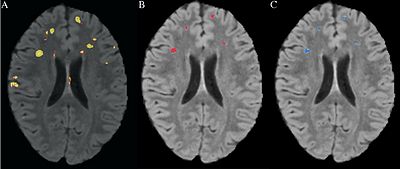

| An Automated Method For Segmenting White Matter Lesions Through Multi-level Morphometric Feature Classification With Application to Lupus. Read more... | ||